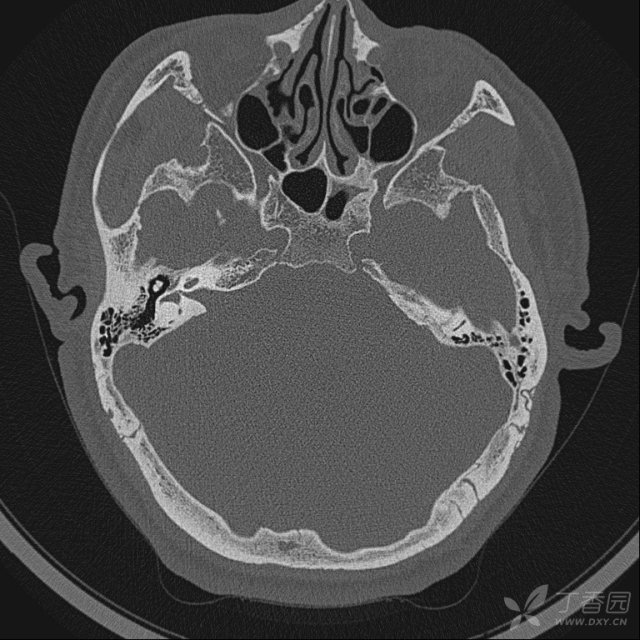

中耳ct:可见鼓室,乳突内软组织密度影.

ct,显示双侧乳突小房气化良好,双侧鼓室内密度增色彩,听小骨_百度知道

【求助】反复中耳炎,这个ct有什么问题?请大侠们给点意见.